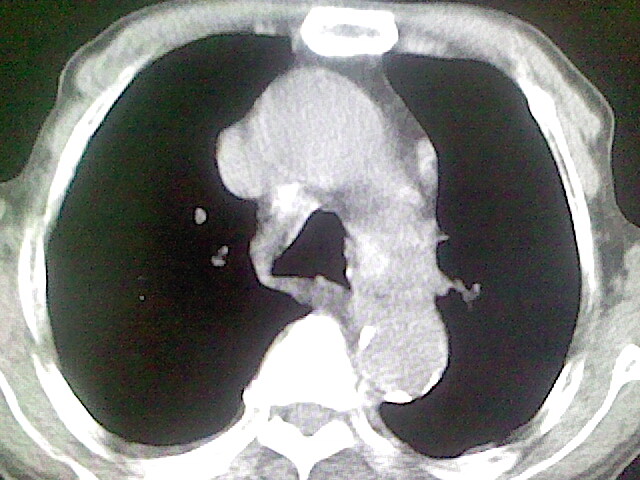

以下是引用zsl6918在2008-8-28 16:49:00的发言:[br]双肺炎性病灶,食管狭窄估计与心房增大压迫所致。

以下是引用xulianj在2008-8-28 20:36:00的发言:[br]慢支肺气肿伴感染,右上肺陈旧性结核;食道建议胃镜检查。

以下是引用wqs571018在2008-8-28 21:18:00的发言:[br]慢支继发感染,右上肺陈旧性结核;食道建议胃镜检查。